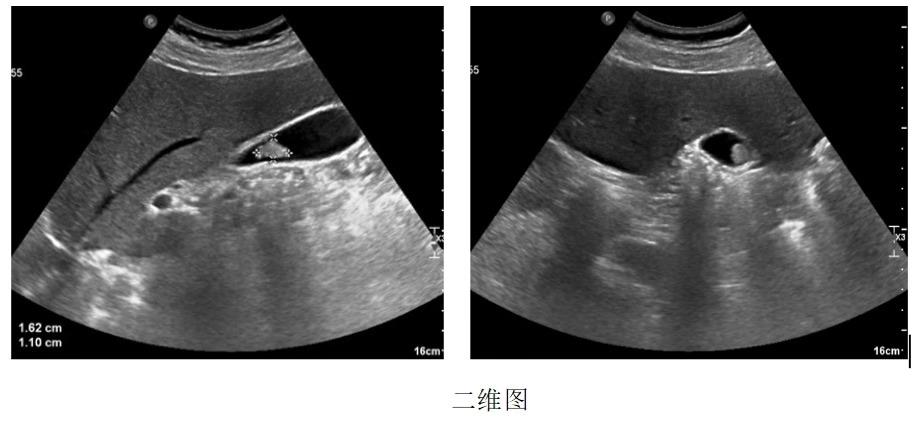

患者男,49岁,2年前体检发现“胆囊息肉”,无疼痛、发热等症状,后定期复查。2019.12彩超复查示:胆囊占位,较前明显增大。欲给予进一步治疗,遂至我院,以“胆囊占位”入住我科。例行超声检查,胆囊内可探及一高回声团,大小约16.2mmx11mm,后伴彗尾,不随体位移动。影像提示:胆囊占位(考虑腺瘤)。

进行胆囊脂餐实验,让患者口服油腻食物,半个小时后再行超声检查,通过前后胆囊的大小变化来判断胆囊的收缩功能。

由此可得,该患者胆囊收缩率约为80%,胆囊收缩功能正常,具有保留胆囊的意义。(一般情况下缩小50%以上,可视为胆囊收缩功能正常)